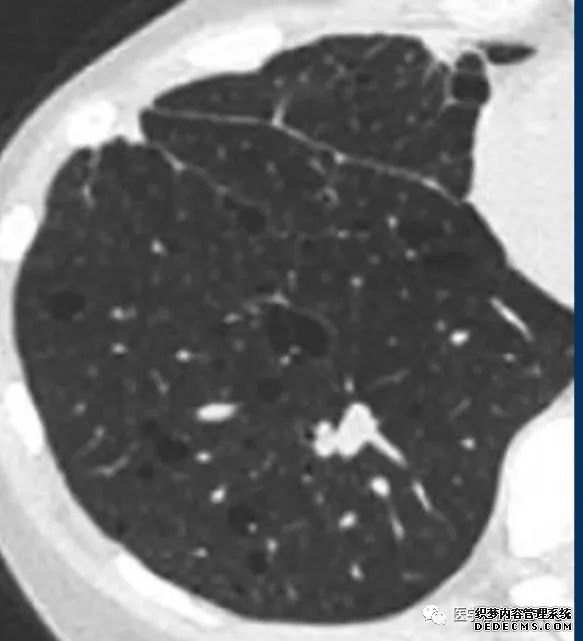

肺转移瘤的十种不典型CT表现